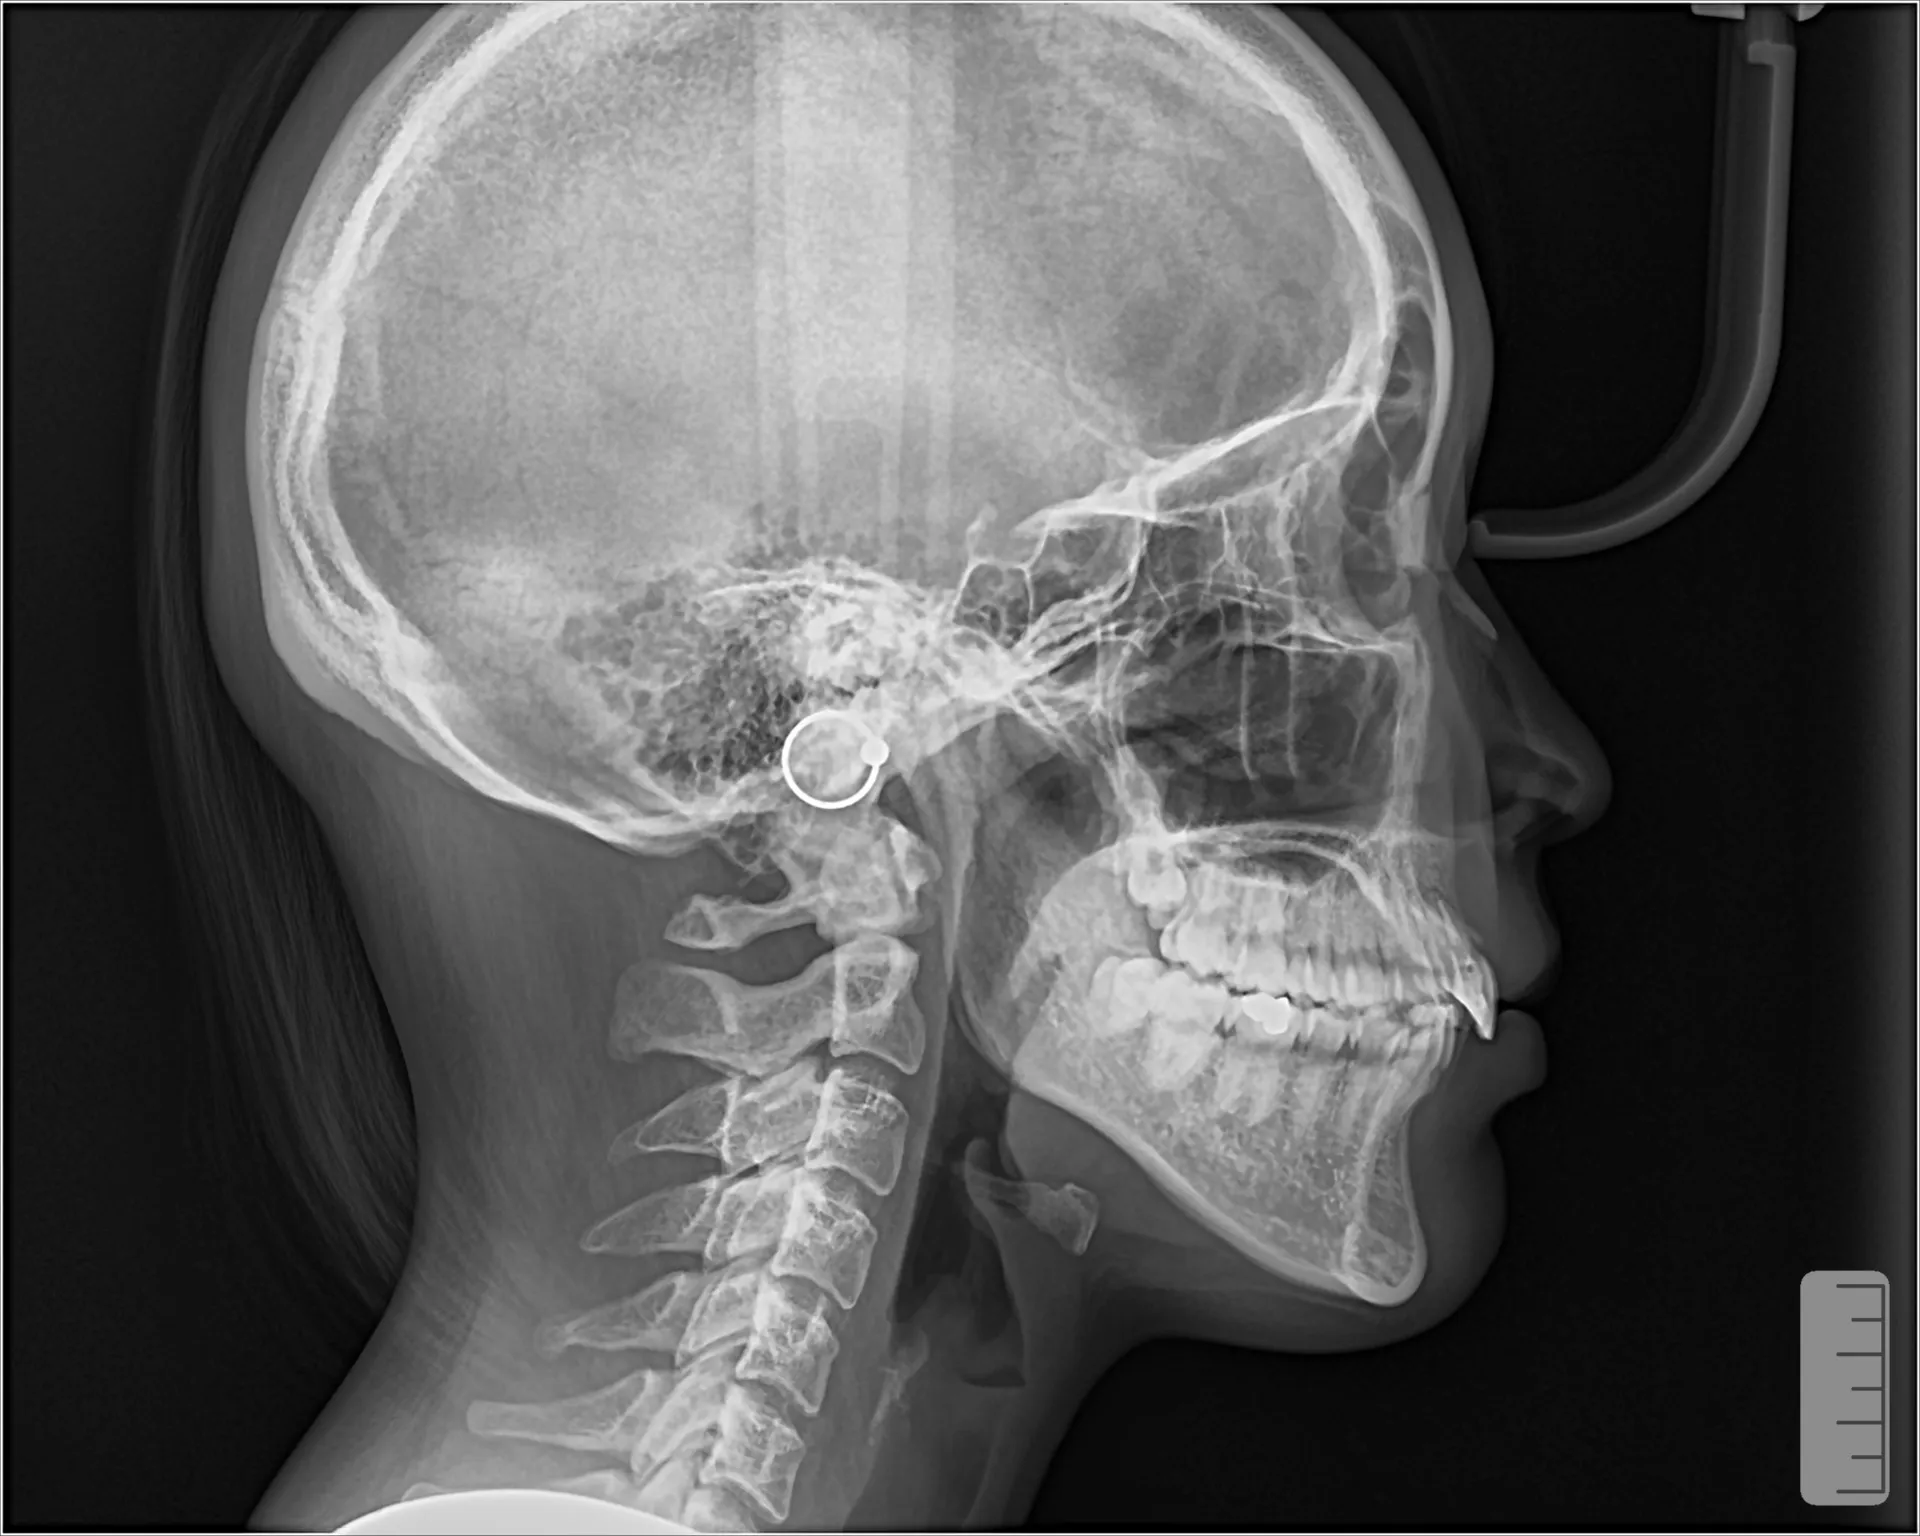

大きく飛び出してしまった前歯の矯正と変色の治療を希望された症例をご紹介いたします。